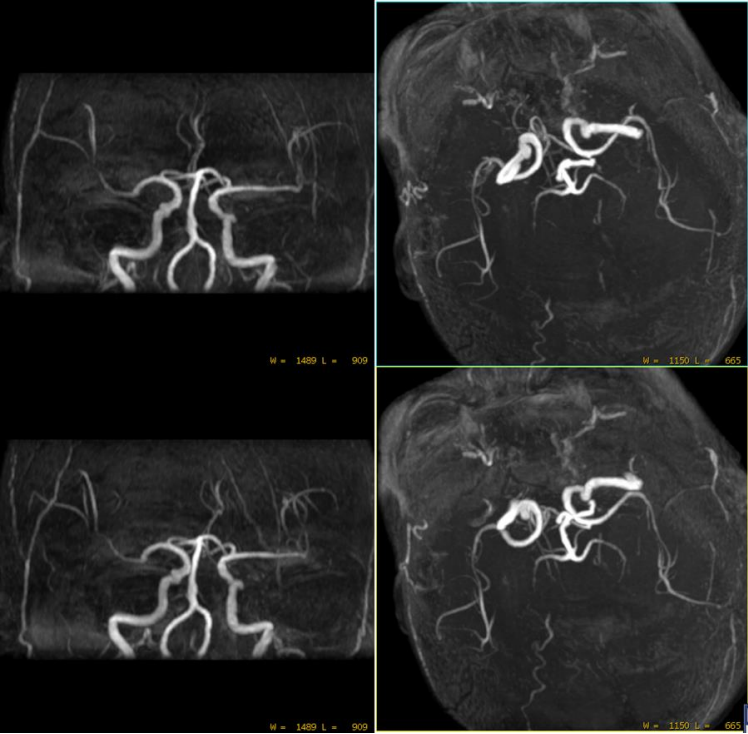

1分半快速TOF MRA两侧血管基本对称 扫描结束,放病人走? 但是患者突发失语症状,如果这么回去,临床如何治疗呢? 想到扫描更薄层图像看下,由于病人有些躁动需要快速扫描,于是扫描了快速薄层CUBE T2FLAIR,Voxel size = 1X1X1mm; 三维加速技术2X2X2,8倍加速,扫描时间2分半钟: